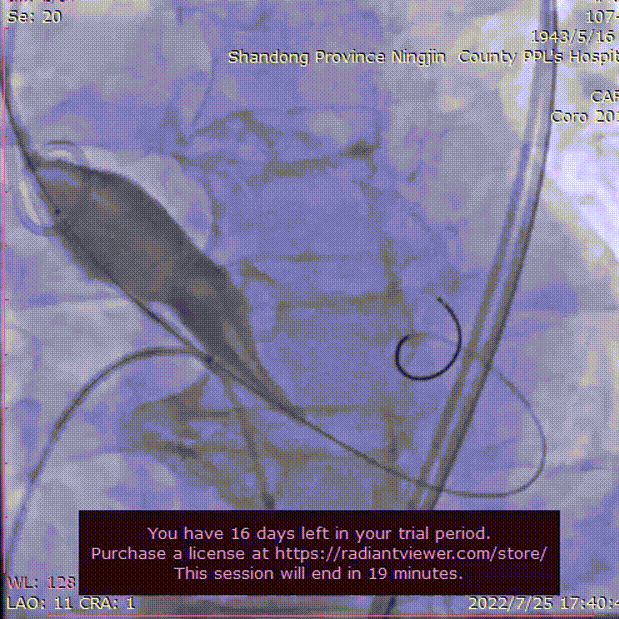

术者团队用25mm球囊预扩,结合瓣环及球囊预扩情况,预装AV29型号瓣膜。患者横位心,在抓捕器辅助下输送器过弓。

球囊预扩

术者团队用22mm球囊预扩,结合瓣环及球囊预扩情况,预装AV26型号瓣膜。

20mm球囊预扩张,结合瓣环及术前策略,预装AV23型号瓣膜并释放至工作位。